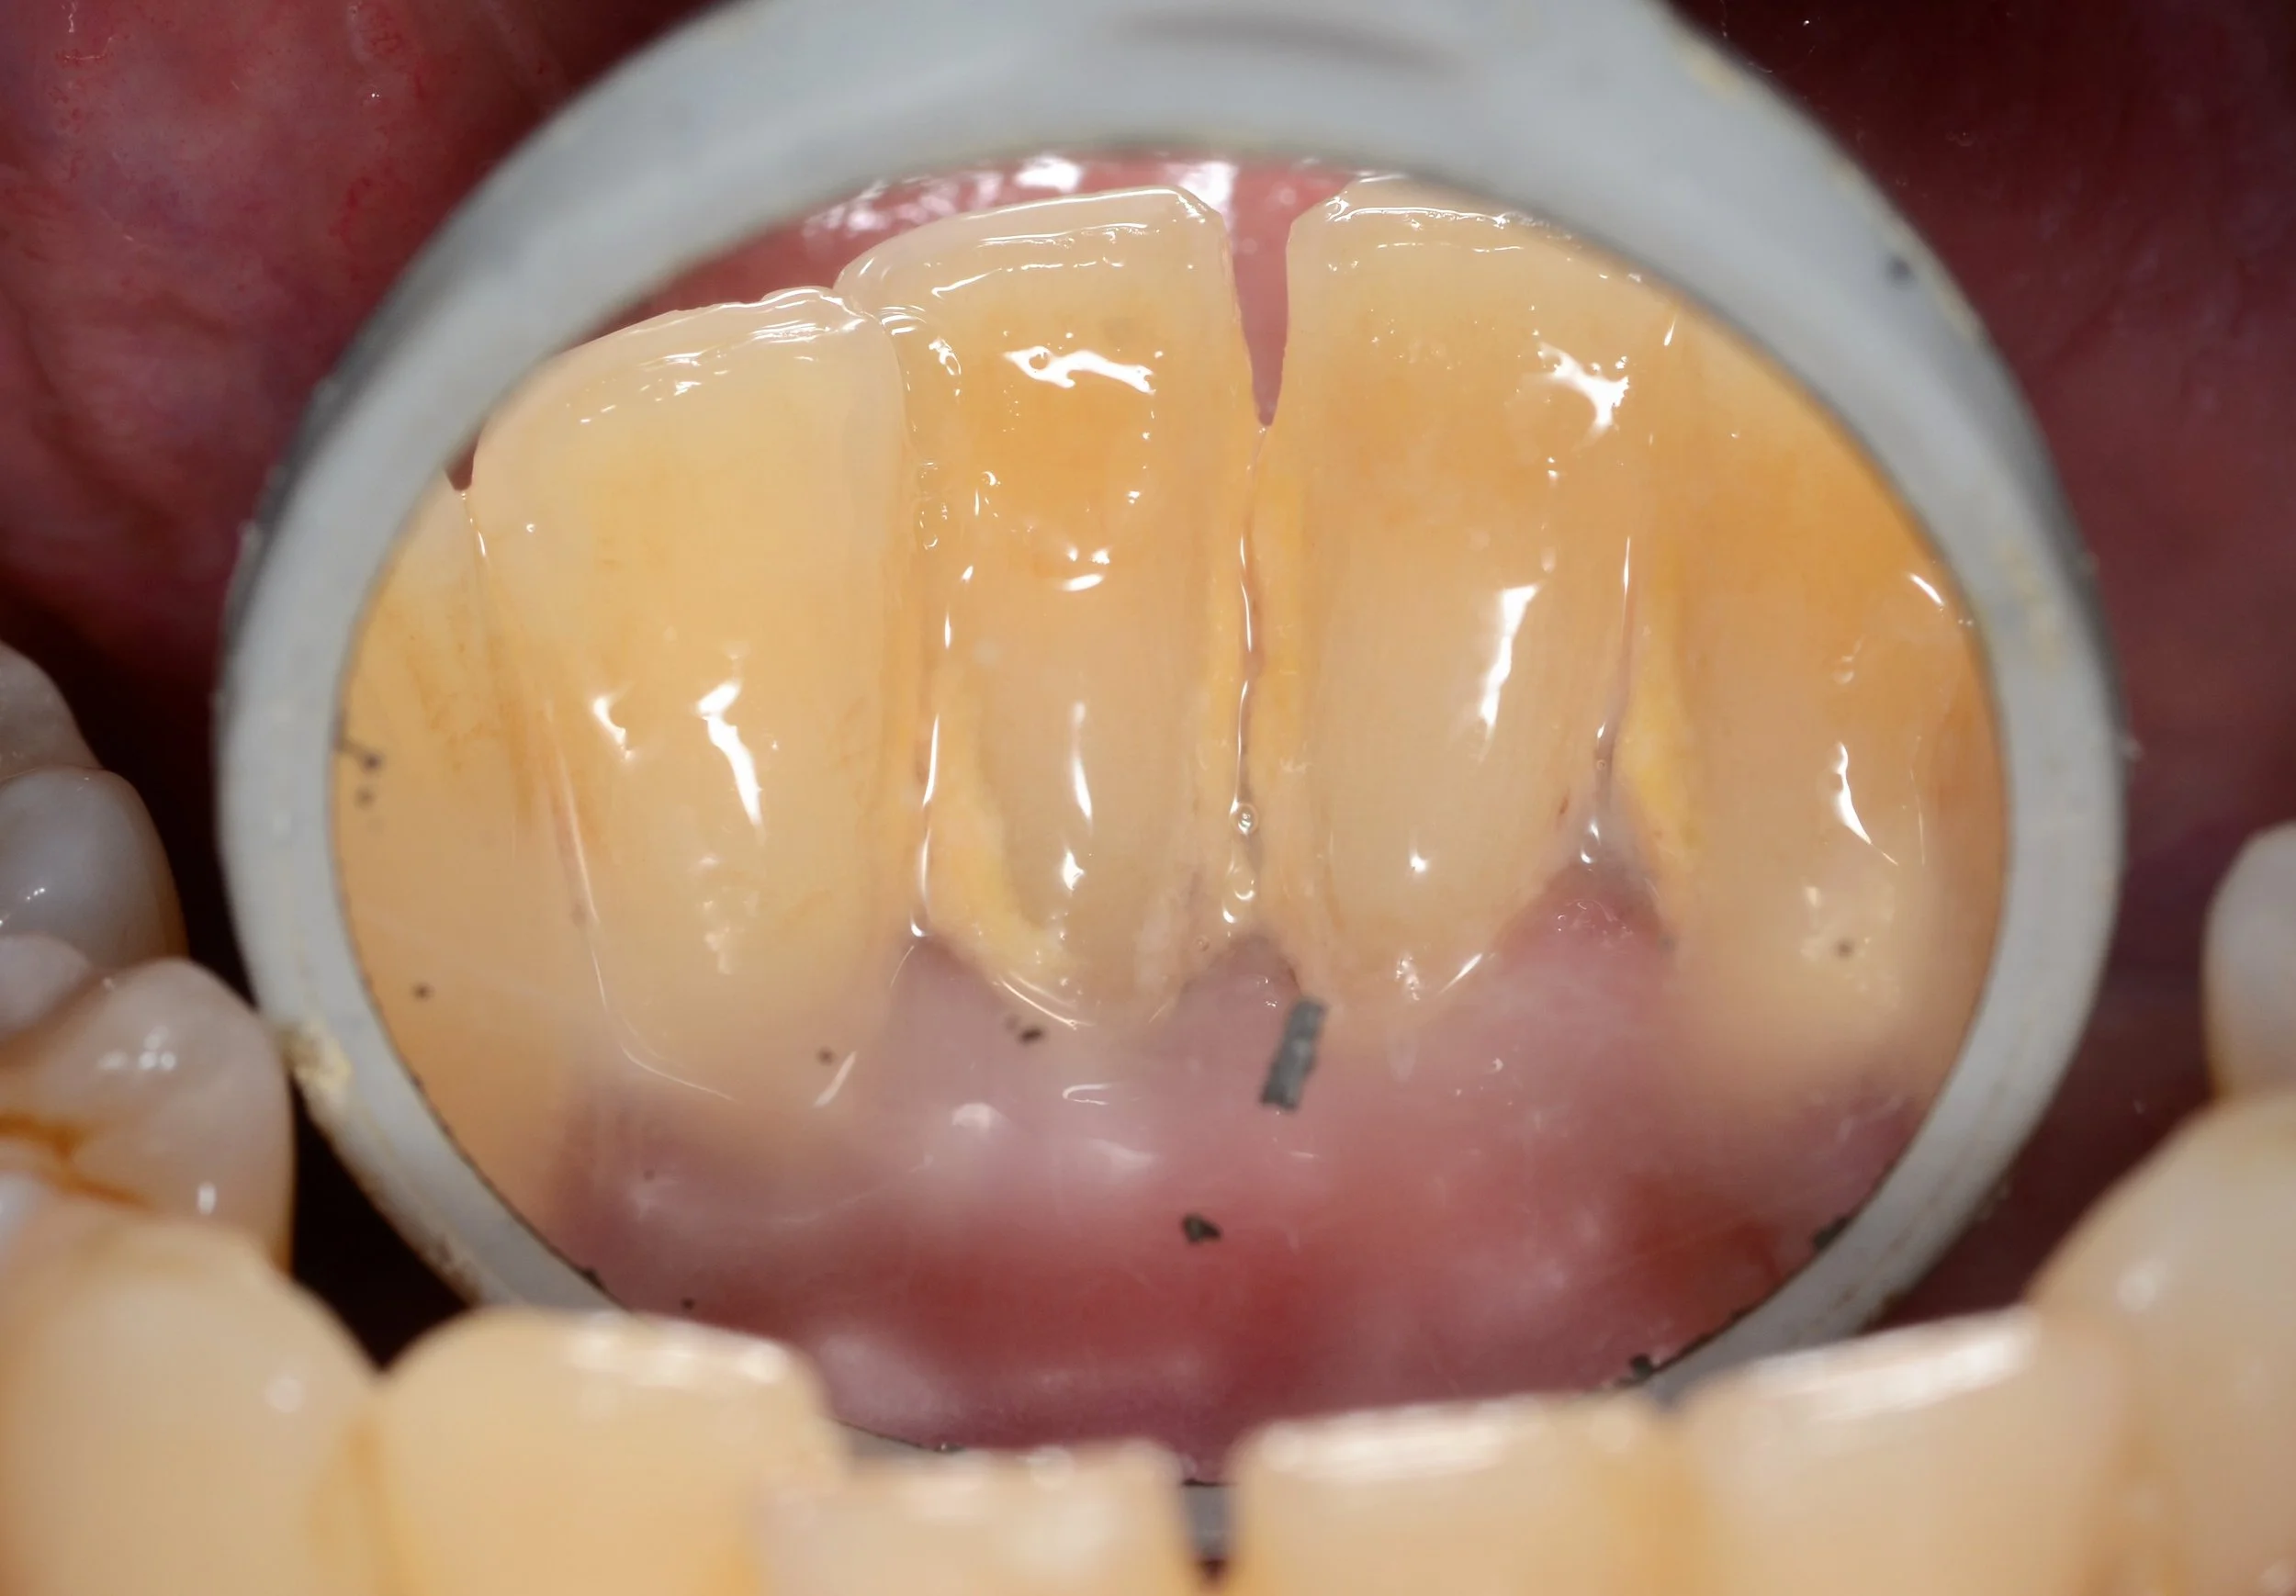

A close up shot of the tongue side of the patient’s lower front teeth.

Deep cleaning halfway done - due to the extensive nature of the patient’s gum disease, it was decided to deep clean the patient’s LEFT SIDE ONLY this visit. The patient will come back at another appointment to finish his deep cleaning on the right side.

We can clearly see the difference between the teeth that have been deep cleaned and teeth that haven’t. The teeth that are clean have this smooth, glass like appearance while the dirty teeth have this rough, yellow, cement like structure attached to them.